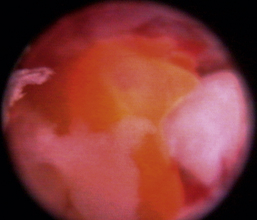

Normal turbinates have a smooth, pink-to-white surface and a spatial alignment that provides channels for the passage of air. The color varies and appears tan in the caudal nasal cavity. Turbinates come in different shapes and sizes, but the surface should be smooth. Ethmoid turbinates in the caudal nasal cavity will have a characteristic stippled or corrugated appearance (Figures 19-13 through 19-16). Ulcerations or various proliferations of the mucosa are indicative of disease. These changes are typically diffuse and accompanied by a lot of mucus. Mucus can be thin to purulent. Copious amounts can be flushed out of the nasal cavity to allow better visibility. The specific disease is determined by biopsy. After full examination of the nasal cavity, run the scope along the floor of the nasal sinus to the level of the choanae. Keeping the scope pointed in a ventral medial direction prevents inadvertent trauma or penetration of the cribriform plate. The index finger of the free hand can be used to follow the scope as it moves caudally over the hard palate; the surgeon can then palpate the scope through the soft palate when it moves into the nasopharynx. Some force is needed to complete this procedure and may result in increased bleeding.

Figure 19-16 Normal canine ethmoid turbinate.

Flexible fiberoptic endoscopes are preferred and utilized effectively by some clinicians, but we do not routinely use them for primary evaluations. Retrograde placement of these scopes behind the soft palate allows visualization of the nasopharynx, choanae, and caudal segments of the nasal passages. Flexible endoscopes can also be used in an antegrade fashion through the nostrils in some patients but are limited by the scope and patient size. Irrigation is limited with small fiberoptic scopes; biopsy instruments are diminutive at best, and the reliability of representative tissue collection should be questioned when this technique is used. The 2.5-mm fiberscope has a single channel used for both irrigation and instrument passage. When an instrument is passed, the irrigation flow is markedly reduced, drastically affecting visualization during biopsy collection. The spatial orientation estimation and direct visualization provided by flexible endoscopes is inferior when compared with rigid telescopes. In most cases, rigid telescopes can be passed through the nasal cavity, choanae, and into the nasopharynx, eliminating the need for flexible retrograde rhinoscopy.